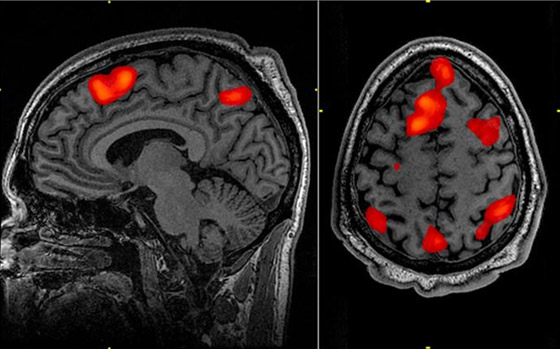

وتم إجراء التسجيل الجديد عندما تعرض مريض يبلغ من العمر 87 عاماً لسكتة قلبية أثناء علاجه من الصرع، حيث قام الأطباء بربط جهاز على رأسه لمراقبة نشاط الدماغ، لكن الرجل توفي أثناء العملية. ومع ذلك، تمكن علماء الأعصاب من التقاط 900 ثانية من نشاط الدماغ عند وقت الوفاة، مما سمح لهم برؤية ما حدث في الثلاثين ثانية قبل وبعد توقف قلبه عن النبض. وأظهرت قياسات الموجات الدماغية قبل وبعد ذلك أن المناطق المعنية بالذكريات والاسترجاع كانت لا تزال نشطة.

وفي وقت لاحق، أصيب المريض بسكتة قلبية وتوفي بينما كان جهاز تخطيط كهربية الدماغ لا يزال يراقب دماغه، مما يوفر أول دليل على ما يحدث في الدماغ قبل لحظات من الموت. وقال الدكتور زيمار في بيان: "قبل وبعد توقف القلب عن العمل مباشرة، رأينا تغييرات في نطاق محدد من التذبذبات العصبية، والتي تسمى تذبذبات جاما، ولكن أيضاً في تذبذبات أخرى مثل تذبذبات دلتا وثيتا وألفا وبيتا".

والتذبذبات الدماغية، أو الموجات الدماغية، هي أنماط متكررة من النبضات الكهربائية الموجودة عادة في أدمغة البشر الأحياء، وتعكس الأنواع المختلفة من الموجات الدماغية وظائف دماغية مختلفة وحالات وعي متباينة. وقال زيمار: "من خلال توليد التذبذبات الدماغية المشاركة في استرجاع الذاكرة، قد يلعب الدماغ آخر استدعاء لأحداث مهمة في الحياة قبل أن نموت، على غرار تلك التي تم الإبلاغ عنها في تجارب الاقتراب من الموت".